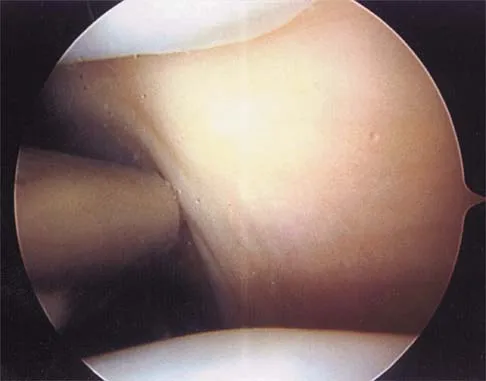

A 24-year-old athlete has a painful right shoulder. Figure 30 shows an intra-articular photograph that was obtained through a posterior portal during arthroscopy; the labrum is indicated by the arrow. Based on these findings, management should consist of